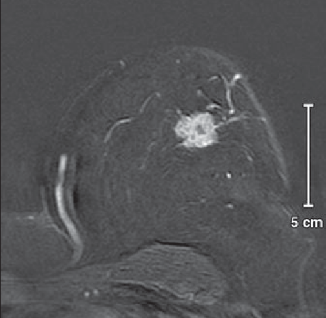

Khi hình ảnh cộng hưởng từ vú (MRI) trở thành một phương thức được chấp nhận rộng rãi hơn để sàng lọc ung thư vú ở những phụ nữ có nguy cơ cao thì tình trạng hormone và chu kỳ kinh nguyệt là những cân nhắc hình ảnh quan trọng.

Trong đa số trường hợp chụp MRI vú, việc sử dụng thuốc đối quang (hoặc tương phản) từ khá phổ biến. Vì thuốc đối quang từ góp phần rất lớn trong việc xác định và phân loại tổn thương dựa vào sự khác biệt ngấm thuốc so với mô nền cũng như tính chất bắt thuốc của chúng.

Thời gian lý tưởng cho MRI của vú là khoảng giữa ngày thứ năm và 15 của chu kỳ kinh nguyệt. Vì trong giai đoạn hoàng thể của chu kỳ kinh nguyệt (từ ngày thứ 15 trở về sau), với sự gia tăng hormone Estrogen và Progesterone gây ra tình trạng phù nề và phát triển thùy tuyến. Điều này dẫn đến sự tăng ngấm thuốc mô vú trong giai đoạn hoàng thể của chu kỳ kinh nguyệt, trong đó tối đa bảy ngày trước khi có kinh nguyệt. Do đó, MRI vú không nên được thực hiện trong thời gian này, mà thay vào đó, giữa ngày thứ năm và 15, đủ lâu sau giai đoạn hoàng thể để giảm bất kỳ sự ngấm thuốc mạnh mô nền gây dương tính giả.

Một hạn chế của MRI vú ở phụ nữ tiền mãn kinh là sự dao động Nội tiết tố trong chu kỳ kinh nguyệt đã gây ra tình trạng tăng ngấm thuốc của gadolinium trong mô vú bình thường khiến việc đánh giá hình ảnh MRI trở nên khó khăn hơn.

Hoặc một số phụ nữ không có chu kỳ kinh nguyệt bình thường để xác định thời điểm chụp MRI tối ưu, ví dụ, phụ nữ tiền mãn kinh đã phẫu thuật cắt tử cung nhưng vẫn giữ được buồng trứng hoạt động bình thường, phụ nữ tiền mãn kinh có chu kỳ kinh nguyệt không đều do uống hoặc tiêm thuốc tránh thai; phụ nữ tiền mãn kinh trải qua hóa trị liệu gây ra với tình trạng quanh mãn kinh và phụ nữ quanh mãn kinh có chu kỳ kinh nguyệt không đều. Do đó, nếu chụp MRI vú trong khoảng thời gian tương ứng với giai đoạn hoàng thể của chu kỳ kinh nguyệt, sự hấp thu của gadolinium có thể gây ra kết quả dương tính giả trên MRI hoặc thậm chí che giấu một ung thư ngấm thuốc bất thường nhỏ, dẫn đến âm tính giả.